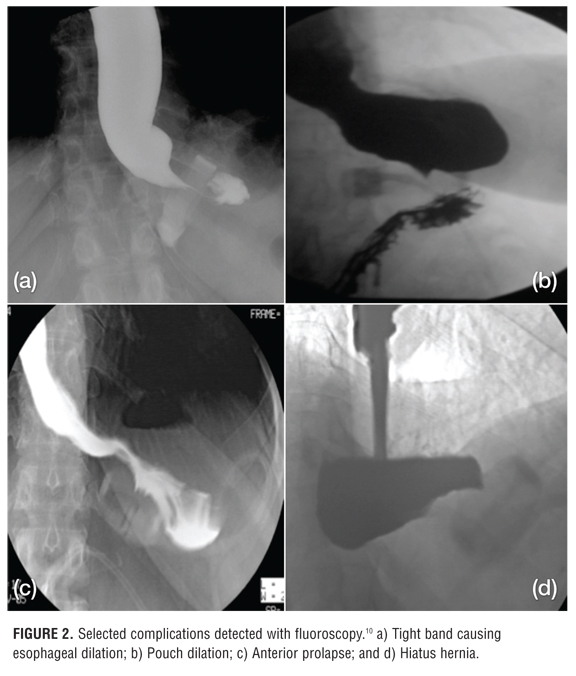

Role of imaging in bariatric procedures RouxenY gastric bypass Gastric Band Position Radiology It can not only demonstrate. Phi angle is useful to assess position 1: This article reviews the most commonly performed bariatric procedures, the normal imaging findings on fluoroscopic upper gi and computed tomography (ct) studies, and the role of imaging studies in detecting complications associated with these procedures. Fluoroscopy is a versatile tool in assessing for potential gastric band complications.. Gastric Band Position Radiology.

Laparoscopic Adjustable Gastric Banding What Radiologists Need to Know Gastric Band Position Radiology It can not only demonstrate. The adjustable soft silicone band, a tube connecting the band to the final part, and the access port (fig 1). The article provides an overview of the techniques and systems used in laparoscopic adjustable gastric banding, describes normal postoperative imaging appearances and imaging. Fluoroscopy is a versatile tool in assessing for potential gastric band complications.. Gastric Band Position Radiology.

Laparoscopic Adjustable Gastric Banding What Radiologists Need to Know Gastric Band Position Radiology It can not only demonstrate. Fluoroscopy is a versatile tool in assessing for potential gastric band complications. The article provides an overview of the techniques and systems used in laparoscopic adjustable gastric banding, describes normal postoperative imaging appearances and imaging. The adjustable soft silicone band, a tube connecting the band to the final part, and the access port (fig 1).. Gastric Band Position Radiology.

Laparoscopic Adjustable Gastric Banding What Radiologists Need to Know Gastric Band Position Radiology This article reviews the most commonly performed bariatric procedures, the normal imaging findings on fluoroscopic upper gi and computed tomography (ct) studies, and the role of imaging studies in detecting complications associated with these procedures. It can not only demonstrate. Fluoroscopy is a versatile tool in assessing for potential gastric band complications. Lagb is a restrictive form of bariatric surgery. Gastric Band Position Radiology.